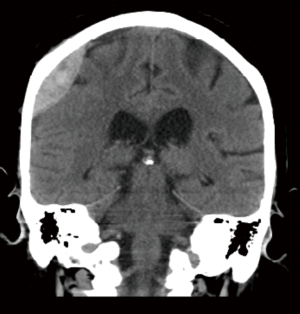

Acute EDHs

The classic presentation of an acute EDH is a loss of consciousness followed by a lucid interval and obtundation in sequence, and a lens shaped hemorrhage on CT (Figure 1). The source of this hemorrhage is typically the middle meningeal artery, however, bleeding may occur from a sinus or the bone itself in the setting of a skull fracture. Indications for operative management are based on imaging and patient status. A volume greater than 30 cc should be evacuated regardless of GCS. If the volume is less than 30 cc or less than 15 mm in thickness on the CT scan or with less than 5 mm of midline shift and GCS greater than 8, the patient may be managed non-operatively. If the decision to proceed to the OR is made, it should be done as soon as possible especially in the setting of GCS <9 or anisocoria. There are no studies that support a single treatment method. A craniotomy, however, does provide more complete hematoma evacuation (39).